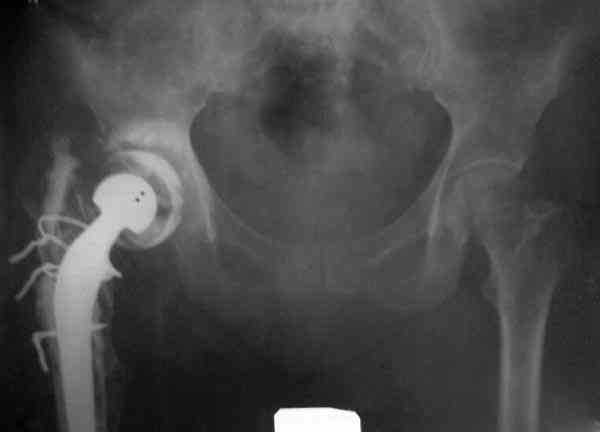

Приглашенный хирург установил ревизионный вариант бедренного компонента без замены ацетабулярного компонента, что осложнилось нагноением и свищами на уровне сустава и средней трети бедра. После двухгодичного безуспешного лечения перевязками и антибиотиками больная обратилась к нам на консультацию.

Повторная операция по удалению тотального протеза с irrigation&debridment, канал после очистки цемента обильно промыт и рассверлен римером.

№3-6 снимки с осложнением

и последние снимки.